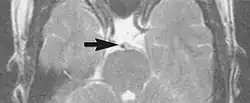

Metal artifacts

Metal artifacts occur at interfaces of tissues with different magnetic susceptibilities, which cause local magnetic fields to distort the external magnetic field. This distortion changes the precession frequency in the tissue leading to spatial mismapping of information. The degree of distortion depends on the type of metal (stainless steel having a greater distorting effect than titanium alloy), the type of interface (most striking effect at soft tissue-metal interfaces), pulse sequence and imaging parameters. Metal artifacts are caused by external ferromagnetics such as cobalt containing make-up, internal ferromagnetics such as surgical clips, spinal hardware and other orthopaedic devices, and in some cases, metallic objects swallowed by people with pica.[3] Manifestation of these artifacts is variable, including total signal loss, peripheral high signal and image distortion (Figs 3 and 4).[1] Reduction of these artifacts can be attempted by orientating the long axis of an implant or device parallel to the long axis of the external magnetic field, possible with mobile extremity imaging and an open magnet. Further methods used are choosing the appropriate frequency encoding direction, since metal artifacts are most pronounced in this direction, using smaller voxel sizes, fast imaging sequences, increased readout bandwidth and avoiding gradient-echo imaging when metal is present. A technique called MARS (metal artifact reduction sequence) applies an additional gradient, along the slice select gradient at the time the frequency encoding gradient is applied.